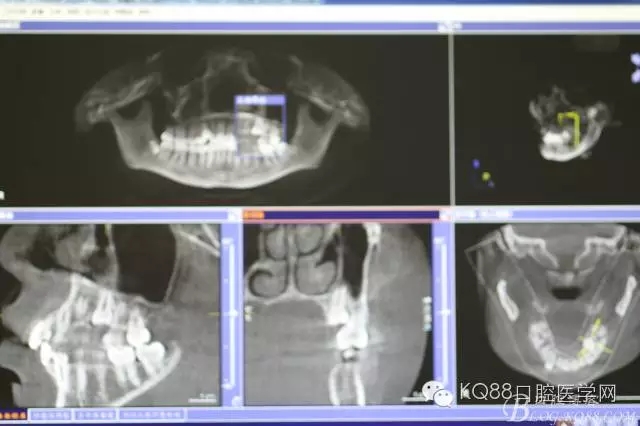

圖3.術(shù)前的CBCT檢查:全景片重建影像,25位于24與26牙根的中1/3處。

圖4.CBCT三維影像顯示:25位于24與26之間的腭側(cè)